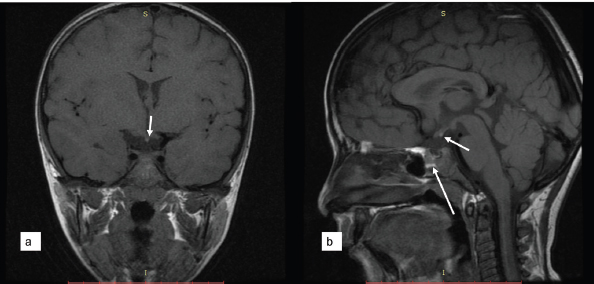

For further evaluation, contrast-enhanced magnetic resonance imaging MRI (CE-MRI) brain with sella protocol was done in our department, the findings of which included hypoplastic anterior pituitary gland with a maximum height of 3 mm (normal height=5.4 ± 1.5 mm) [1] and an ectopically placed posterior pituitary bright spot at the level of the optic chiasma. The pituitary stalk was not visualized (Figure 1a and b). No other significant abnormality was seen. Based on these CE-MRI features, the radiological diagnosis of pituitary stalk interruption syndrome (PSIS) was made.

Figure 1. (a) Sagittal and (b) coronal T1 weighted MRI image showing bright posterior pituitary spot at optic chiasma (small white arrow in a and b), and hypoplastic anterior pituitary in the sella turcica (large white arrow in a) with non-visualization of the pituitary stalk.